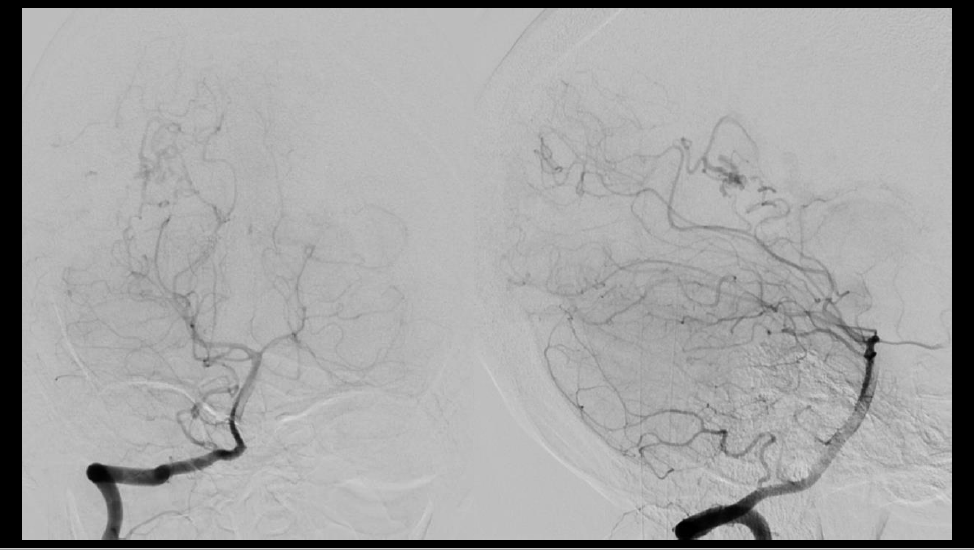

Tratamiento combinado de malformación arteriovenosa con sangrado reciente